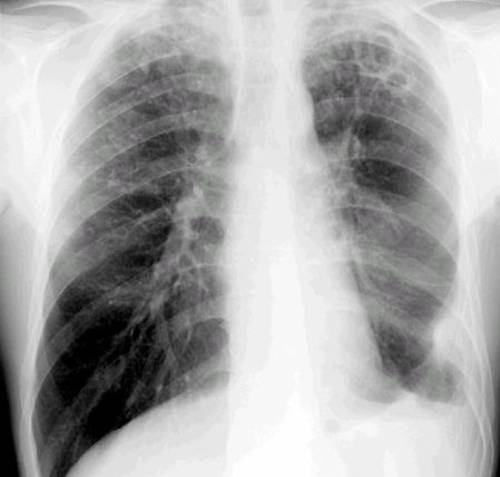

- Röntgenuntersuchung der Lunge